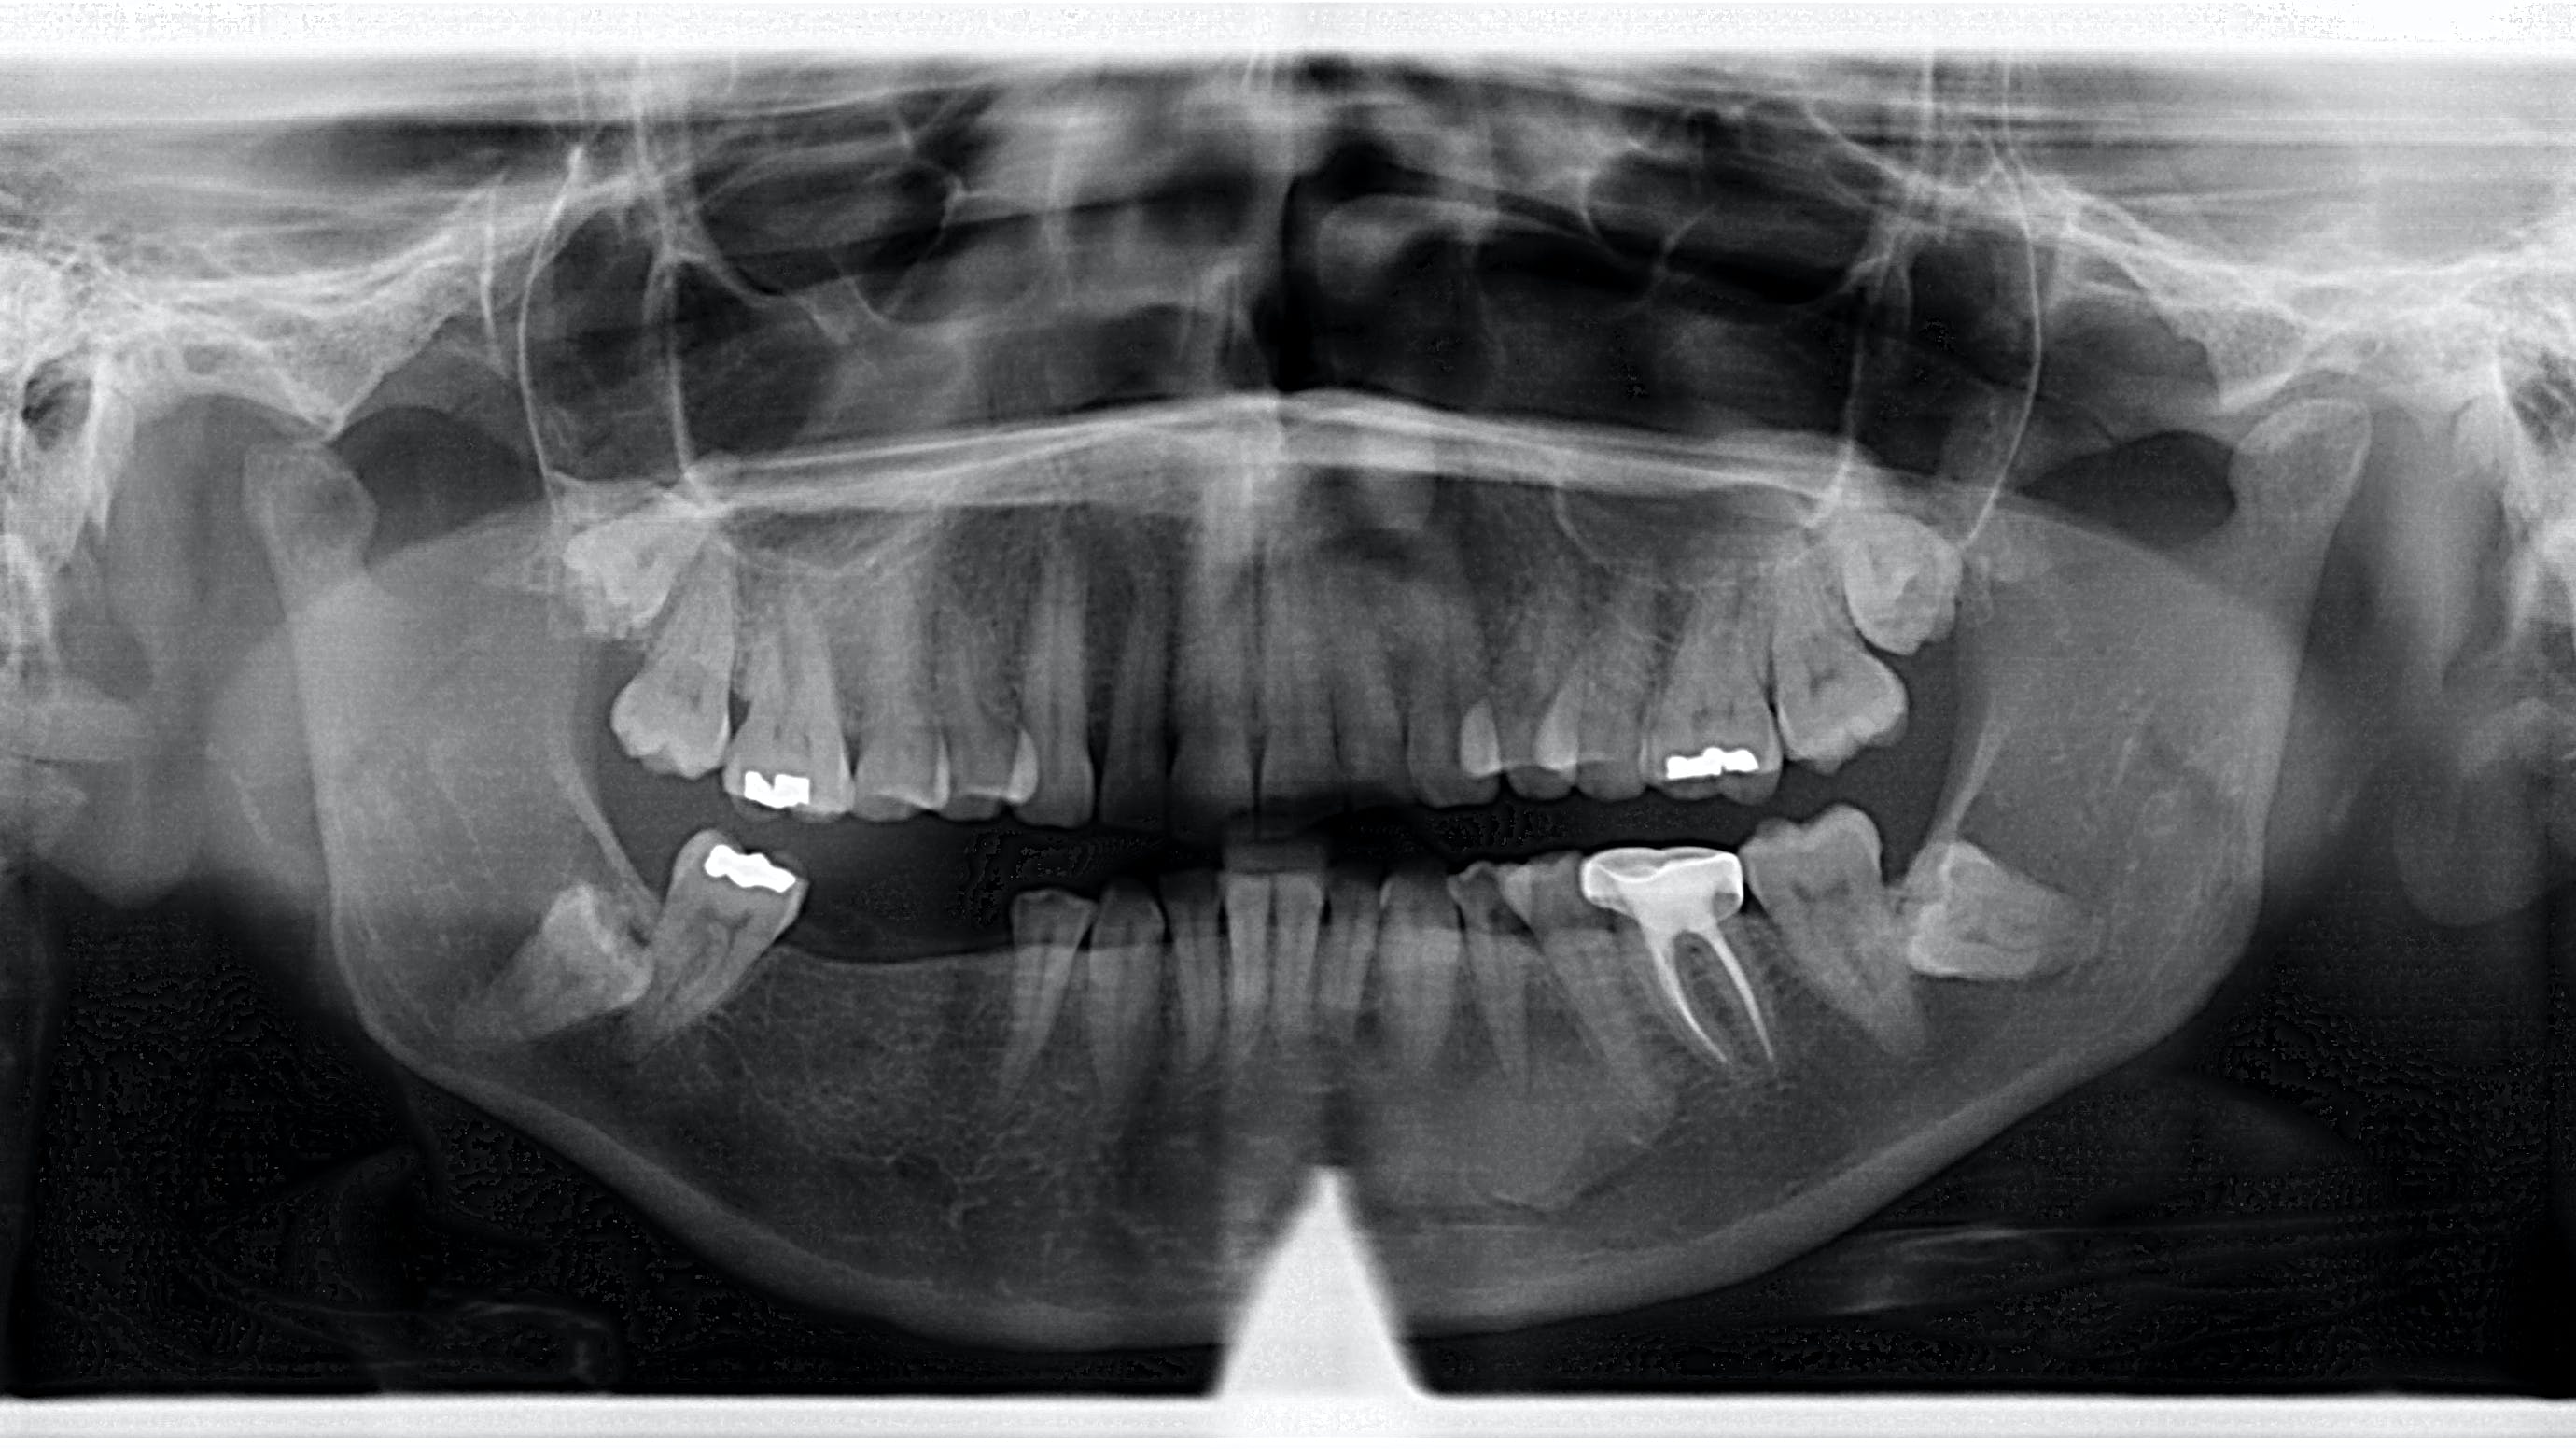

A panoramic radiograph revealed an almost-vague radiodense lesion on the lower left side, around the apices of teeth nos. 20–22, measuring approximately 3 cm x 1.5 cm. The lesion was nonpalpable, the area was not tender to palpation, and the patient was unaware of its presence.

Definitive diagnosis: Idiopathic osteosclerosis

Since this patient presented with no neurosensory changes, cortical expansion or displacement or resorption of adjacent teeth, and its cause could not be readily explained, it is consistent with a diagnosis of idiopathic osteosclerosis. The patient continues to be recalled periodically to assess for changes in this area.